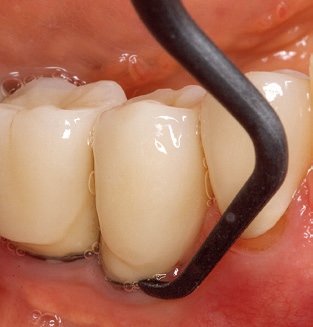

L'attuale piano di lavoro per SPT

Naturalmente, l'uso di strumenti per la rimozione meccanica del biofilm è una componente centrale di SPT e quindi di importanza primaria. Di conseguenza, il flusso di lavoro SPT comprende sia la pulizia sopra-gengivale che sub-gengivale. Nel nostro piano di lavoro, una combinazione di strumenti manuali e

di dispositivi per la pulizia meccanica si è dimostrata vantaggiosa. Sono disponibili diverse opzioni per le procedure meccaniche: dispositivi sonici, dispositivi ad ultrasuoni e dispositivi di air-polishing.

Una buona illuminazione del campo di lavoro facilita notevolmente il processo. Il sistema utilizzato dagli autori ottiene questo risultato grazie a un anello LED 5x integrato nel manipolo. Naturalmente, viene offerta anche una serie di consigli di lavoro per diverse indicazioni. Un inserto diritto, utilizzabile universalmente, è lo strumento di base necessario per la pulizia meccanica dei denti naturali (Fig. 5a e b). Sono disponibili anche inserti curvi, che consentono l'accesso alle forcazioni esposte, per le aree difficili da raggiungere nella regione posteriore (Fig. 6).